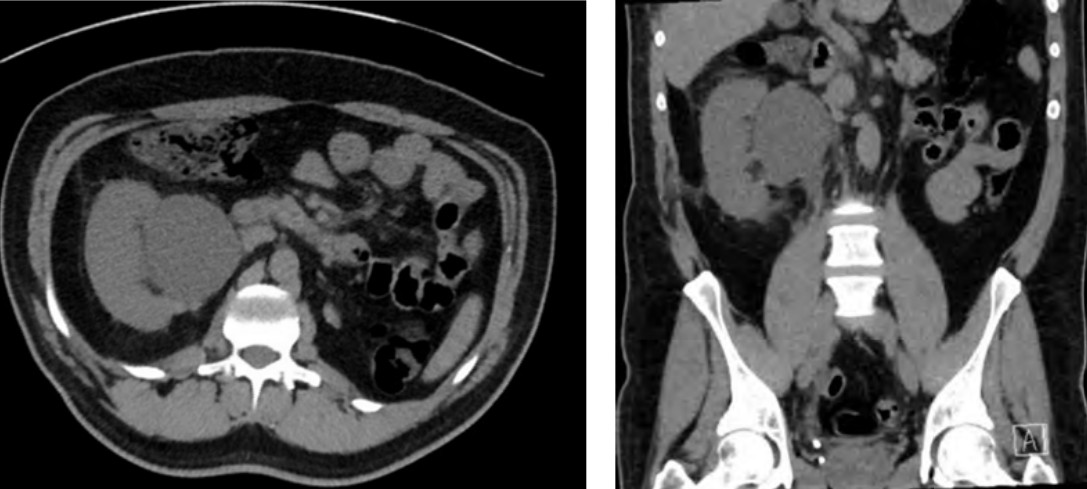

A 42-year-old man with known autosomal dominant polycystic kidney disease (PCKD) has presented to the ED with flank pain.